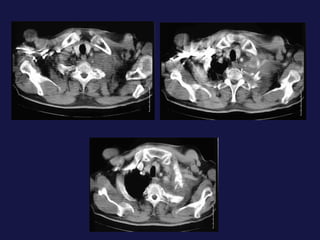

Extensión local y a distancia. Afectación  hiliar Invasión de la pared torácica (Pancoast). Afectación  pleural ( 8-15%). Afectación mediastínica. Linfangitis carcinomatosa. Metástasis extratorácicas.

Extensión local ya distancia. Afectación hiliar Invasión de la pared torácica (Pancoast). Afectación pleural ( 8-15%). Afectación mediastínica. Linfangitis carcinomatosa. Metástasis extratorácicas.

Metástasis. Cerebro. Hueso.Hígado. Suprarrenales.